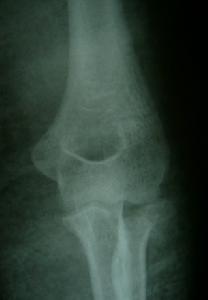

橈骨頭表面被有軟骨,中部凹入呈杯狀與肱骨小頭關節面相對。當肘關節伸直時,僅橈骨頭之前半部與之相接觸。屈肘時兩者全吻合,杯狀面之尺側為一半月形的傾斜面,於鏇前時與滑車之橈側邊緣相接觸,

橈骨頭周邊也被有軟骨,稱柱狀唇(cylindricalrim),與尺骨之橈骨切跡組成上尺橈關節。橈骨頭並非正圓形,而系橢圓形。北京積水潭醫院在新鮮尺體上測定的結果為長軸24mm,短軸21mm,長短軸之比為8∶7。兒童的發病率較低,多發生在成年人。

橈骨小頭骨折(一)裂紋型為線狀骨折無移位,骨折線多從外下斜向後上達關節面,環狀韌帶無損傷,對骨折起到穩定作用,故不易再移位。

直接外力引起的骨折,很少見。常見的是肘關節伸直位摔倒,手掌著地,外力使橈骨頭在外翻位與肱骨小頭撞擊而產生骨折。常合併肱骨小頭損傷與內側副韌帶損傷。多見於成年人且容易漏診。若不能得到早期治療,有些患者前臂鏇轉功能受到限制,不得不將橈骨小頭切除。根據骨折形態,分以下類型。

(一)裂紋型為線狀骨折無移位。骨折線多從外下斜向後上達關節面。環狀韌帶無損傷,對骨折起到穩定作用,故不易再移位。

(二)塌陷骨折橈骨頭關節面被壓而塌陷。

(三)粉碎骨折無移位者仍保持橈骨頭的外形,仍有完整的關節面。環狀韌帶完整。有移位者,環狀韌帶多有損傷。